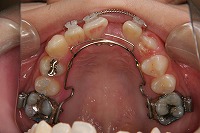

10歳4か月 | 10歳10か月 | 11歳1か月 | 11歳3ヵ月 | 11歳4か月 | 11歳7か月 | 11歳8か月 | |

反対咬合と前歯が生えてこない事を主訴に来院された、10歳4か月の男の子です。診断「下顎骨の過成長による骨格性反対咬合で上顎正中の左方偏位と埋伏歯を伴う」1期治療で反対咬合の解消と埋まっていた前歯を牽引しました。